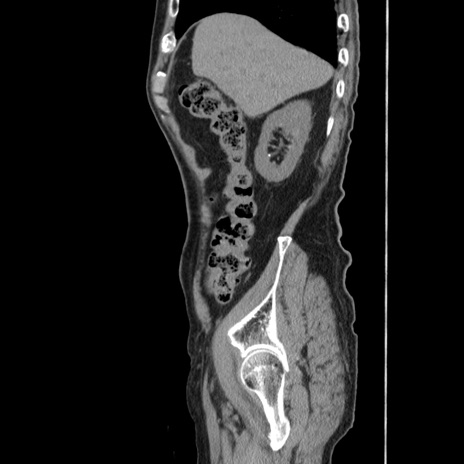

冠状断像

【症例】80歳代男性

【主訴】左側腹部痛、嘔吐

【現病歴】本日早朝より左腹部に痛みあり。昼頃嘔吐認めたため、救急要請。

【既往歴】直腸癌(Mile手術)、胆摘

【身体所見】意識清明、BT 35.9℃、BP 221/93mmHg、SpO2 97%(RA) 、腹部:左ストーマ周囲に限局性の腹部膨隆あり。 膨隆部自発痛・圧痛あり・軟。

【データ】WBC 7700、CRP 0.09